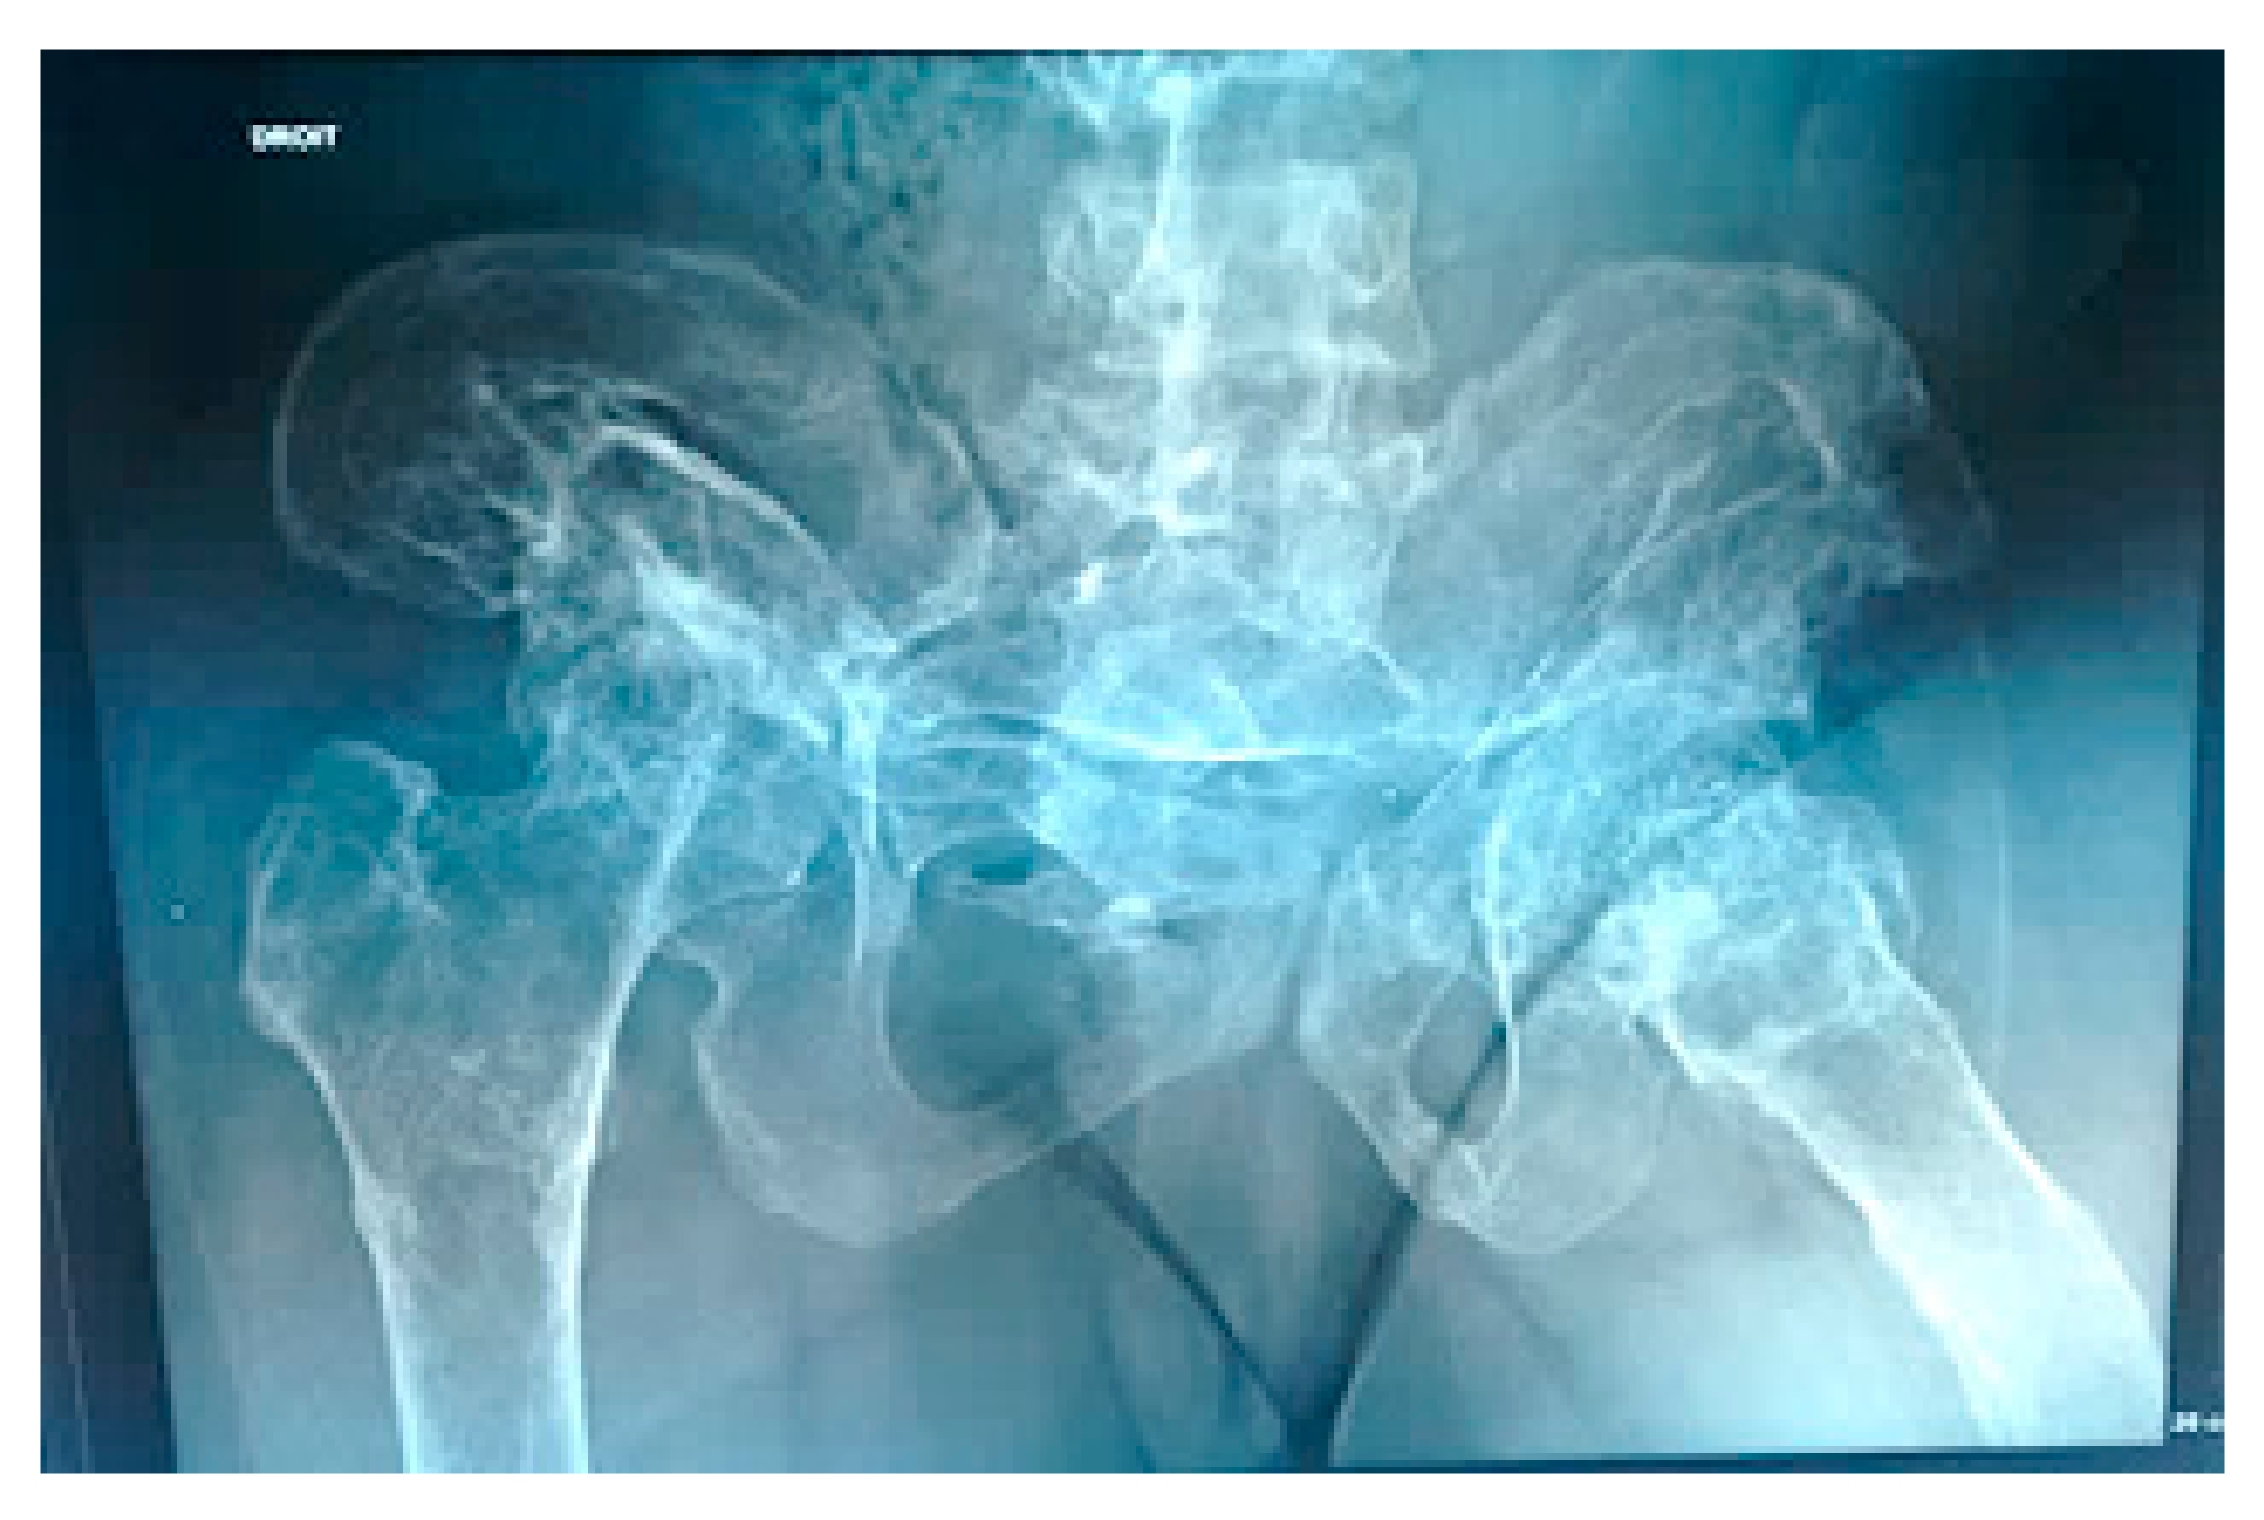

3.2. Group II: Patients with Progressive Disorganization of the Weight Bearing Joints Associated with Painful Dissolution of the Long Bones